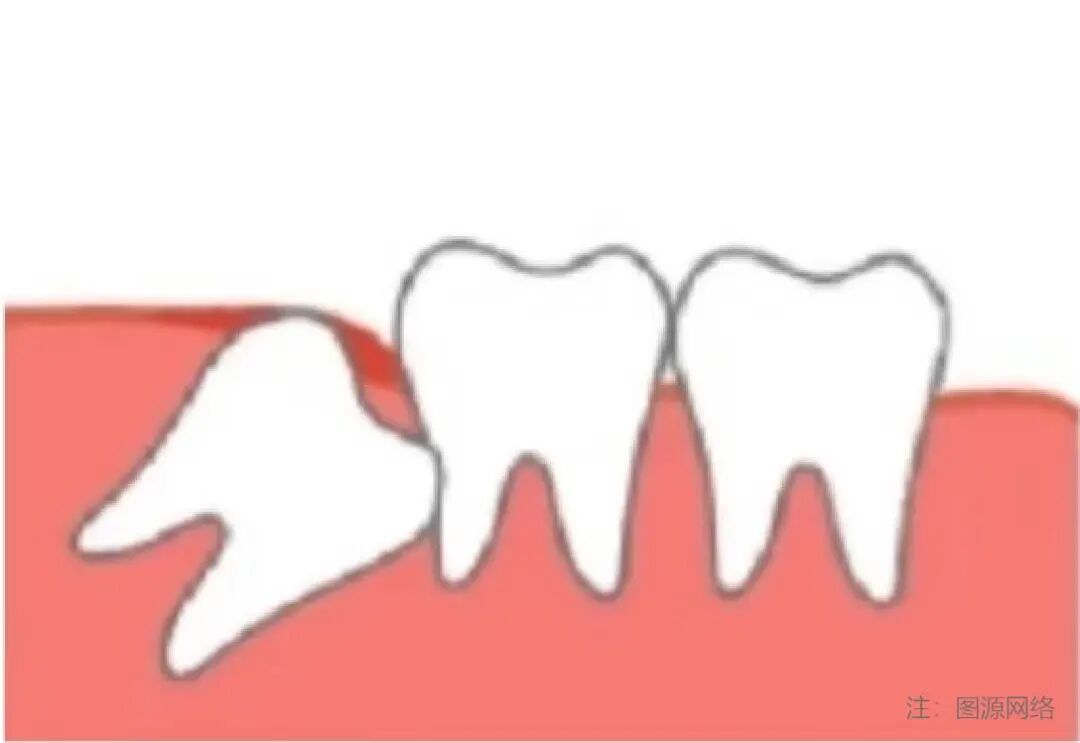

阻生齿-09.jpg

4)侵犯邻牙:邻牙不易清洁,容易龋坏/压迫牙根,引起牙根吸收